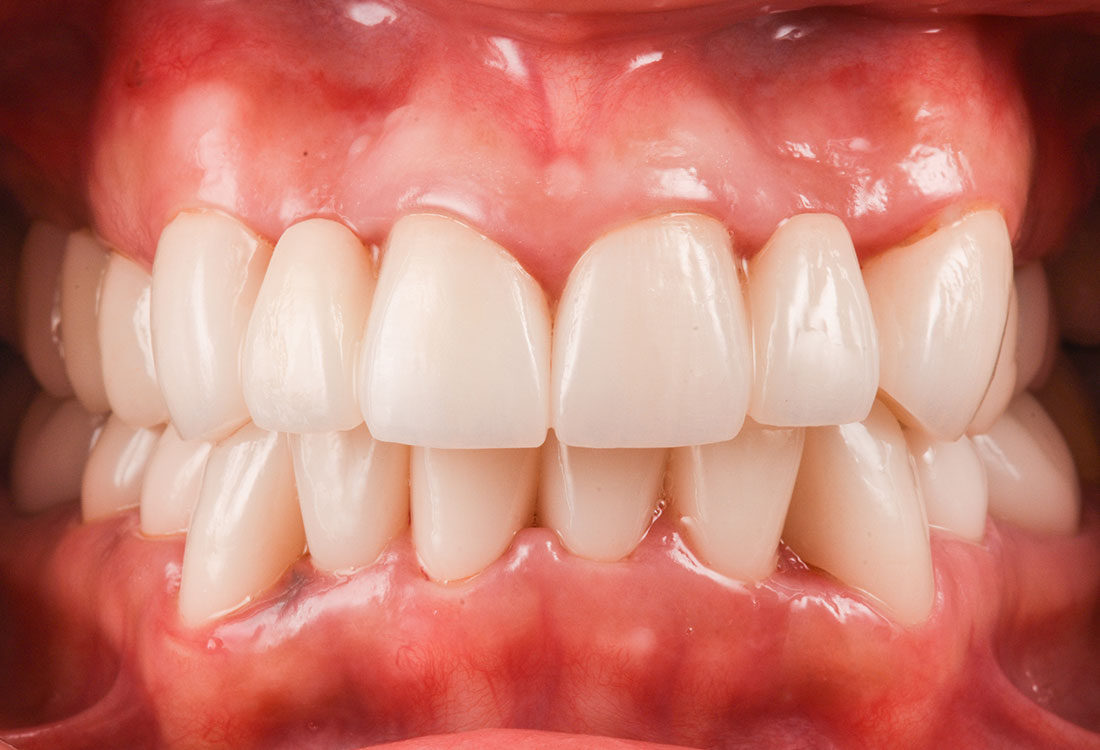

治療症例 Case1

Treatment cases

ご相談内容

- 歯並びが気になる

- 矯正をする時間が取れないので被せ物で治していきたい

治療前

治療後

今回は前歯をグラデーションカラーのジルコニア、奥歯をセレックで治療しました。

見た目の美しさのポイントになるスマイルラインも整っています。